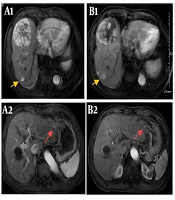

Unexpected Anti-tumor Effect of Selective Internal Radiation Therapy and Radiofrequency Ablation Followed by Immune Checkpoint Inhibitors for Hepatocellular Carcinoma